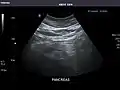

Right kidney

Kidneys: Right and left kidneys measure 11.5 cm and 12 cm in length respectively. No hydronephrosis. Small left lower pole kidney cyst.